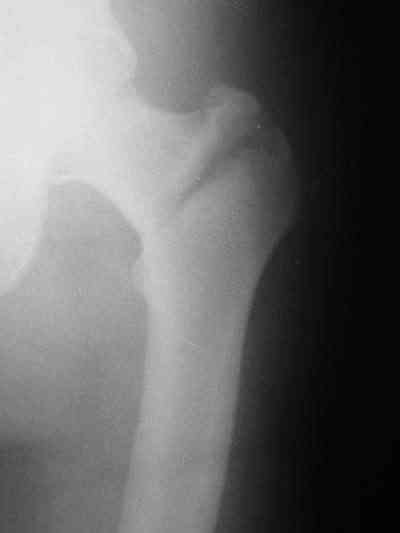

Качество снимков приемлемое. С нагрузкой категорически не надо спешить - только при уверенных рентгенологических признаках сращения на обоих уровнях в данном случае. Т.е. не только на диафизе, но и в вертельной области. При безупречном синтезе DHS ранняя нагрузка в этой зоне была бы безопасна, все определялось бы сращением диафиза. А поскольку винт в DHS сделали ну о-очень короткий, то ойкнуть не успеете, как

проксимальный отдел бедра в варус кувыркнется.